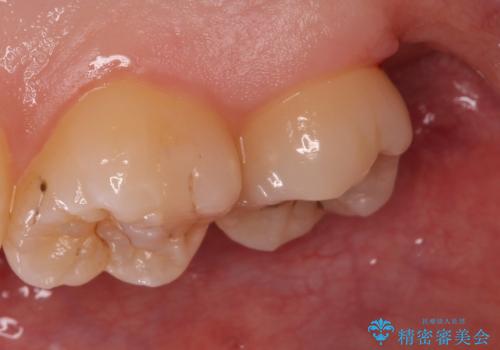

[ 歯肉縁下齲蝕 ] 歯周外科を行った虫歯治療

![[ 歯肉縁下齲蝕 ] 歯周外科を行った虫歯治療の症例 治療前](https://seimitsushinbi.jp/wp/wp-content/uploads/2023/05/a64b0434e936f69092c4868d7fec9b97-500x350.jpg?v=1684994566)

![[ 歯肉縁下齲蝕 ] 歯周外科を行った虫歯治療の症例 治療後](https://seimitsushinbi.jp/wp/wp-content/uploads/2023/05/fa1958073cf4724216bea0bd1890c46a-500x350.jpg?v=1684994581)

歯の高さを出すための親知らず抜歯と歯肉切除

担当医 岡田康成